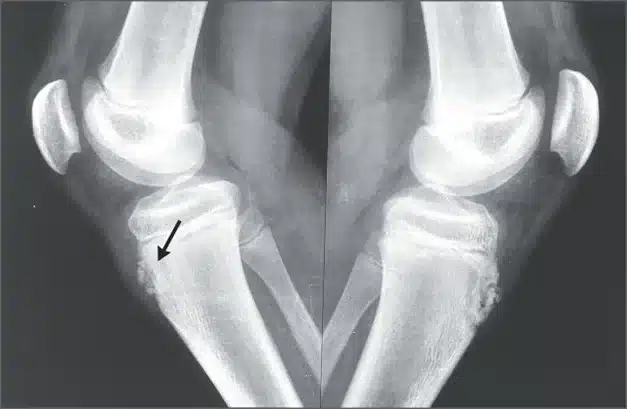

La enfermedad de Osgood Schlatter es una patología descrita por Ogden como una avulsión que ocurre en el núcleo de osificación, afectando la tuberosidad anterior de la tibia.

La enfermedad de Osgood Schlatter ocasiona dolor e inflamación a nivel de la rodilla, así como un crecimiento progresivo de la tuberosidad tibial anterior; sin embargo, la intensidad de estos síntomas puede variar según el paciente.